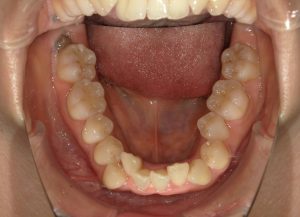

治療前→治療後(下顎)